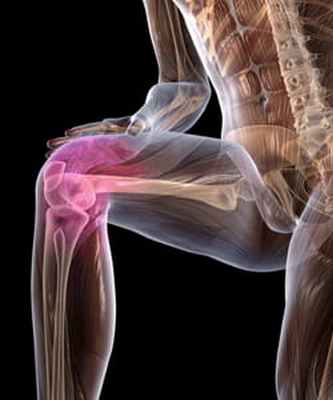

Зачастую дегенерации подвергаются опорные суставы, такие как тазобедренные и коленные. При поражении тазобедренного сустава заболевание именуют коксартрозом. Последний сопровождается болью в паховой и ягодичной области, приводит к хромоте и укорочению конечности. Гонартроз обозначает поражение коленных суставов и проявляется ограничением подвижности, венозным застоем и болью.

При остеоартрозе чаще всего поражаются тазобедренные (коксартроз) и коленные (гонартроз) суставы, межфаланговые суставы кистей, хотя от этой болезни не застрахован ни один сустав.